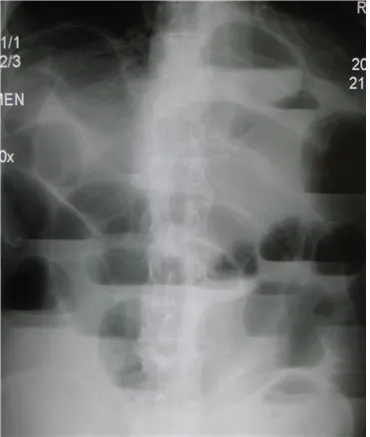

82세 여성이 3일 전부터 복부 팽만감을 호소하며 가스 배출이 없고 대변을 보지 못했다. 6년 전 대장암 수술로 인한 일부 대장 절제술을 시행받았다. 혈압은 128/80 mmHg, 맥박은 76회/분, 체온은 37.2℃로 측정되었다. 복부는 팽만해 있었지만, 특별한 압통이나 반발압통은 관찰되지 않았다. 복부 X선 및 CT를 통해 진단을 시도하였다. 적절한 치료 방법은 무엇인가?

AXR, APCT: stepladder sign

Imp: 소장폐색(small bowel obstruction)

• 복부팽만, 변비를 호소하는 환자의 AXR, APCT상 stepladder sign 및 small bowel dilatation이 관찰되어 소장폐색으로 진단할 수 있다.

• 환자의 복부 수술력(대장암 수술)으로 인한 adhesion이 장폐색의 원인일 가능성이 높다.

• V/S stable하고 압통, 반발압통이 관찰되지 않아 교액의 가능성은 낮고, 따라서 응급 수술을 진행할 필요는 없다.